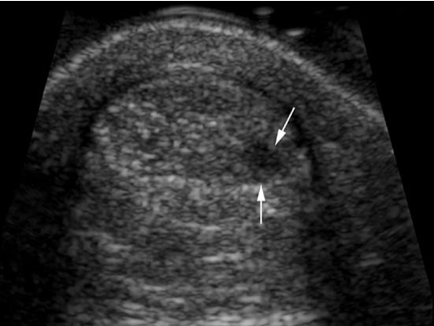

Patient de 37 ans, vient vous voir avec une douleur au-dessus du talon. Il dit avoir repris la course en ce moment. Que voyez- vous à l’imagerie ?

Tendinopathie focale.

Le tendon calcanéen apparaît en coupe axiale.

Tendon calcanéen globalement augmenté de volume et on visualise un nodule intratendineux arrondi et hypoéchogène (↑).